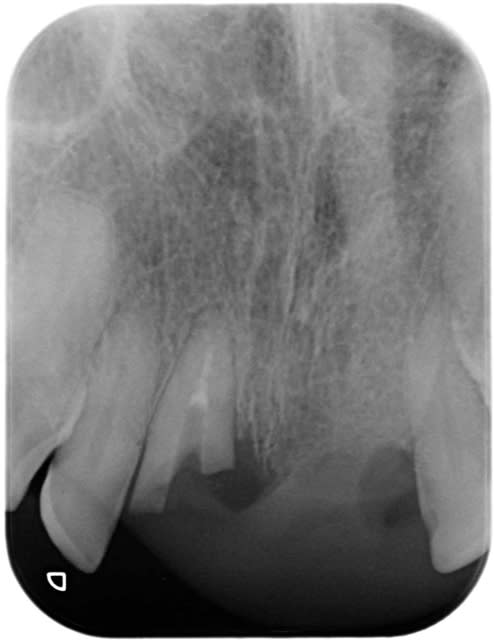

mets la rvg de la 23 et éteins ton plafonnier

tu ne vois rien au niveau de la couronne (impression qu'elle est cruantée en périphérie par ailleurs au niveau de la chambre pulpaire impression de rhyzalyse interne----)carie

un exemple plus parlant d'une 13 totalement incluse et totalement cariée

13 incluse   carie djskg2 - Eugenol